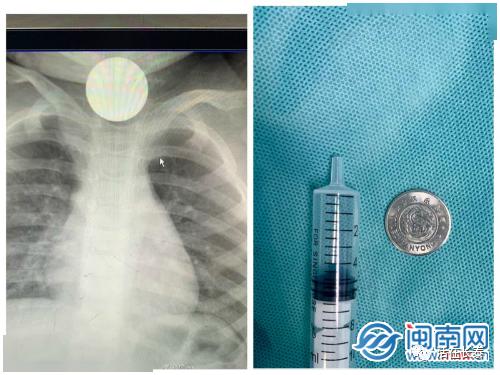

案例一:1岁宝宝吞下游戏币,紧急就医

近日,一位家长带着1岁多的宝宝来到医院,原来宝宝在玩耍时不小心吞下了一枚游戏币。医生通过手术,成功将游戏币取出,宝宝目前已无大碍。